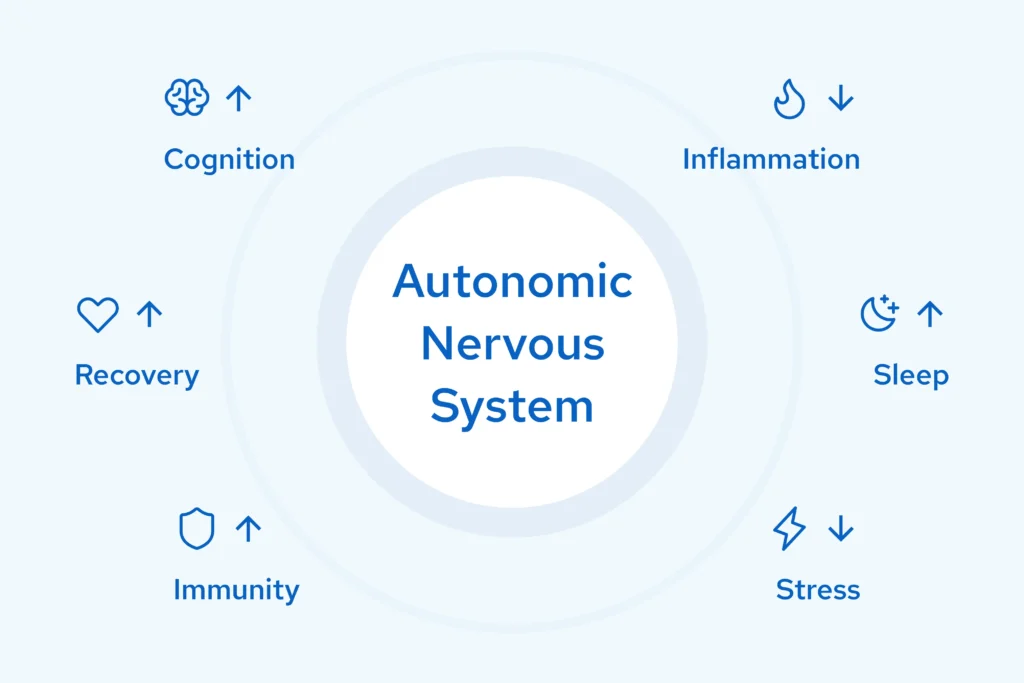

When your autonomic system loses balance, everything deteriorates: energy, recovery, cognition, resilience. Most people accept this decline. The science says you don’t have to.

Optimizes Autonomic Balance: The Key to Longevity

Your autonomic nervous system controls everything that keeps you alive without conscious thought: heart rate, digestion, immune response, hormonal balance.

When it’s out of balance, you age faster.

Your Nervous System Determines How You Age

Most longevity protocols focus on what you put in your body. Few address the system that controls how your body uses everything you give it.

Your autonomic nervous system regulates recovery, inflammation, sleep, cognition, and stress response: the pillars of healthy aging.

- When it's dysregulated, every other intervention works less effectively.

- When it's supported, everything else works better.